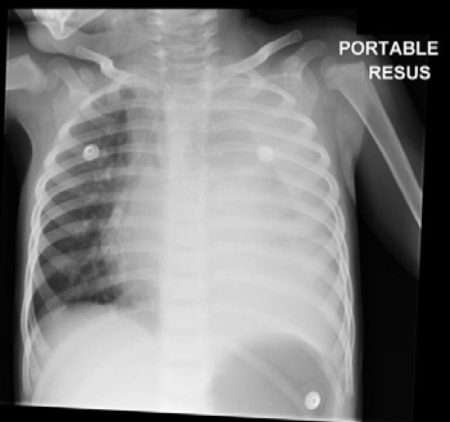

Chest x-ray of complicated pneumonia, showing opacification of the left lung field consistent with a large pleural effusion and empyema. There is associated right-sided bronchial wall thickening and consolidation

Haq IJ, et al. BMJ 2017 Mar 2; 356: j686. doi: 10.1136/bmj.j686; used with permission